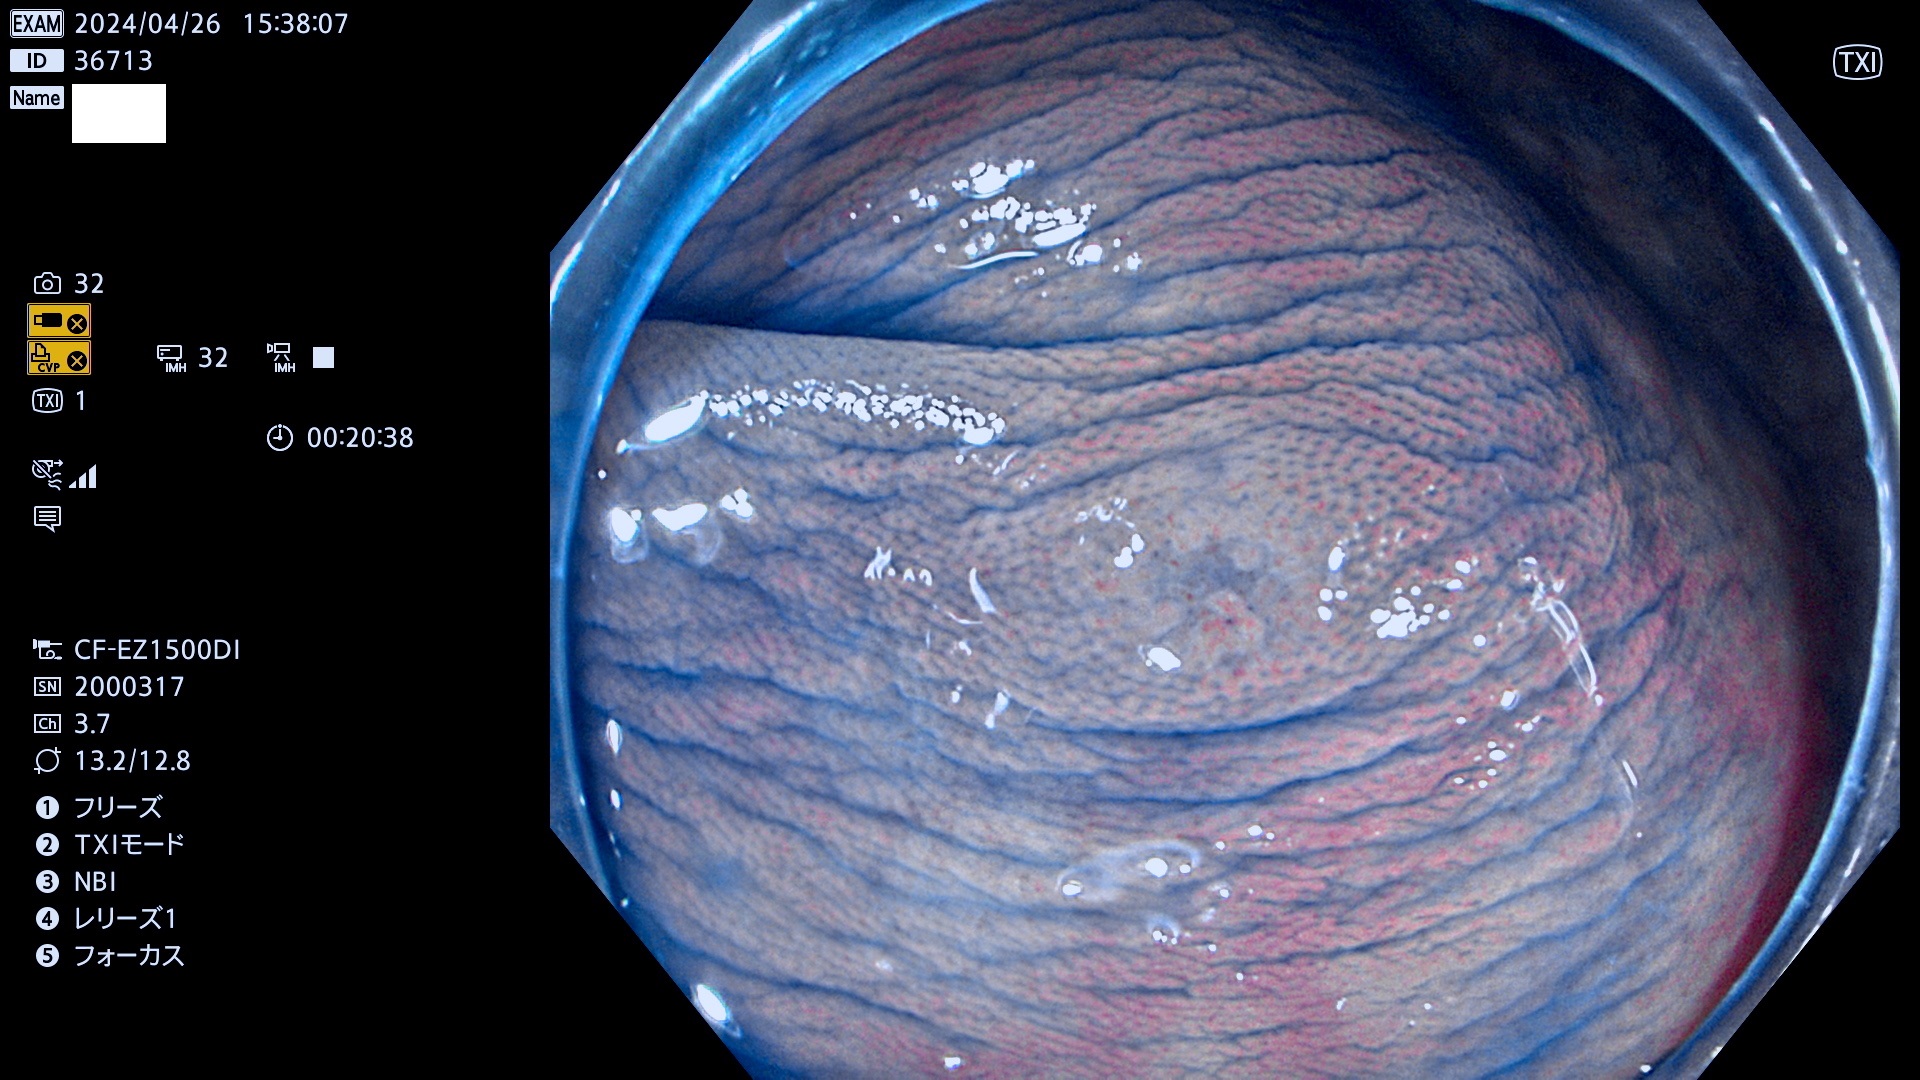

表面型腺腫(Flat Adenoma)の中で、完全に平坦な物をUb、陥凹している物をUcと呼びます。平坦隆起型(Ua)よりも、発見が難しく危険な病変です。

抽出の対象期間 2024年4月25日〜4月29の5日間(50件の検査)7件 (7/50=14%)